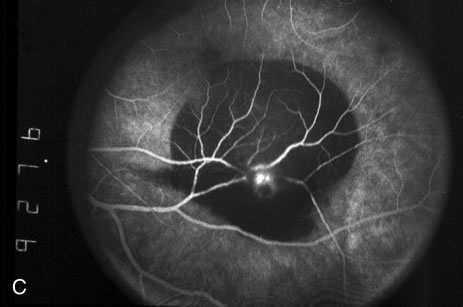

Fig. 2. A. Color fundus photograph of a 200-micron macroaneurysm that arises from a retinal artery near the optic disc with thin subretinal hemorrhage that does not threaten the fovea. B. The midphase fluorescein angiogram reveals blockage of choroidal but not retinal vascular hyperfluorescence. C. The late-phase angiogram demonstrates staining of the macroaneurysm.[pa[et[ol0]

Because of rapid blood flow through retinal arterial macroaneurysms, they typically fill quickly in the early phase of the fluorescein angiogram. In the mid- and late-phases of the angiogram, the macroaneurysm tends to leak to varying degrees, depending on its perfusion and endothelial integrity (Fig. 3C). If there is subretinal fluid surrounding the aneurysm, there may be pooling of dye into the subretinal space. In some cases, a characteristic Z-shaped kink may be identified at the site of the aneurysm.

Perfusion abnormalities caused by the macroaneurysm cause changes in the surrounding retinal vasculature as well, and this is best visualized on fluorescein angiography (Fig. 3B). Ischemia from stagnation of blood flow results in capillary telangiectasis, microaneurysm formation, and capillary nonperfusion.

Some or all of these angiographic features may be obscured by blood or lipid exudation from the aneurysm. If blood collects in front of the retinal vessels (vitreous hemorrhage, preretinal hemorrhage, subinternal limiting membrane hemorrhage, or intraretinal hemorrhage), then blockage of hyperfluorescence may be partial or complete. Subretinal blood blocks hyperfluorescence from the choroid but not the retinal circulation, resulting in dramatically distinct retinal vessels against a dark background (Fig. 3B,C). Lipid exudation and retinal edema may cause partial blockage of hyperfluorescence.